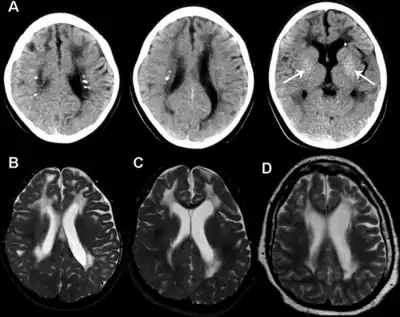

Neuroradiology: The spectrum of neuroradiological features associated with AGS is broad,[35][36] but is most typically characterised by the following:

- Cerebral calcifications: Calcifications on CT (computed tomography) are seen as areas of abnormal signal, typically bilateral and located in the basal ganglia, but sometimes also extending into the white matter. Calcifications are usually better detected using CT scans (and can be missed completely on MRI without gradient echo sequences (magnetic resonance imaging)).

- White matter abnormalities: These are found in 75-100% of cases, and are best visualised on MRI. Signal changes can be particularly prominent in frontal and temporal regions. White matter abnormalities sometimes include cystic degeneration.

- Cerebral atrophy: is seen frequently.